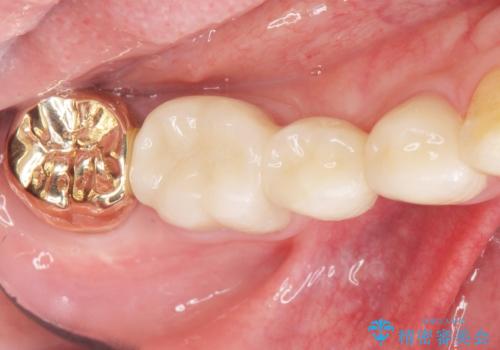

親知らずを抜歯して隣の歯のう蝕を除去し、歯肉の治癒をしっかり待ったのち、患者様のご希望によりゴールド(PGA)クラウンによる補綴を行いました。

ゴールド(PGA)クラウンの自然な咬み心地とブリッジの審美的な仕上がりに喜んで頂けました。

右下7:ゴールド(PGA)クラウン